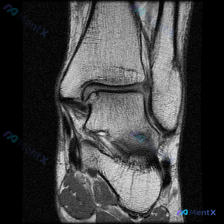

刚看到这个病例,临床提问是"影像中可见什么?",临床判断是存在软组织积液,我整理了完整的影像分析和临床思路分享给大家。 一、病例影像基础信息 这是一张踝关节MRI轴位T2序列单帧图像,先给大家整理影像读片结果: 1. 骨与关节:胫骨、腓骨远端形态正常,骨髓腔无异常信号,踝关节间隙清晰,未见骨质破坏、...